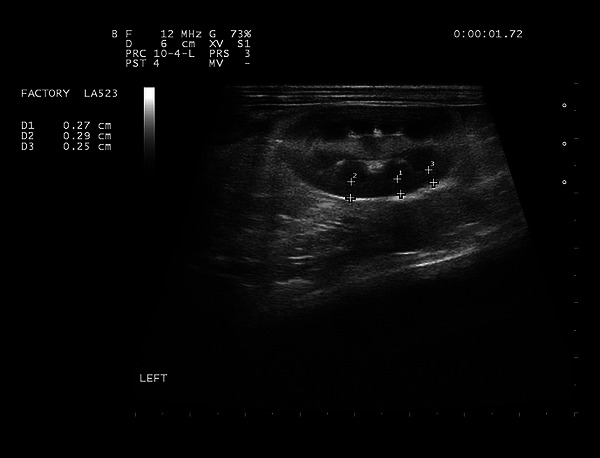

Methods: Sixty healthy adult male mixed-breed rabbits underwent ultrasonographic evaluation. Renal cortical thickness and abdominal aortic diameter were measured, ensuring that only rabbits without clinical or ultrasonographic signs of kidney disease were included.

Results: Pearson correlation analysis revealed a positive correlation between renal cortical thickness, aortic diameter and body weight. However, the ratio of renal cortical thickness to aortic diameter remained independent of body weight.

Conclusions: This study established a normative reference range for renal cortical thickness relative to aortic diameter in rabbits, providing a novel diagnostic parameter for renal assessment. The confidence intervals for the ratio were 0.82 (0.77-0.87) to 1.35 (1.30-1.40) for the left kidney and 0.79 (0.74-0.84) to 1.33 (1.27-1.38) for the right kidney, marking the first report of this method in the literature.